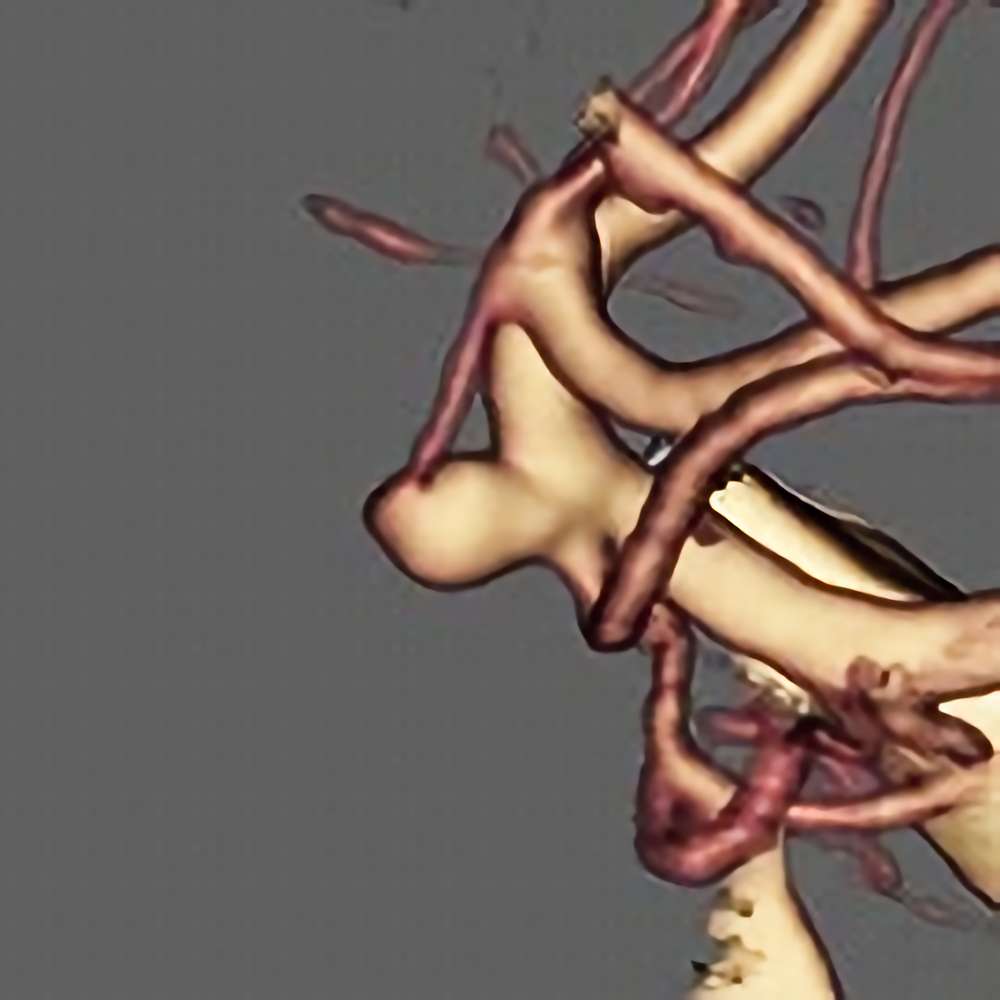

脳動静脈奇形

血管塞栓術

松田/濵田/元永